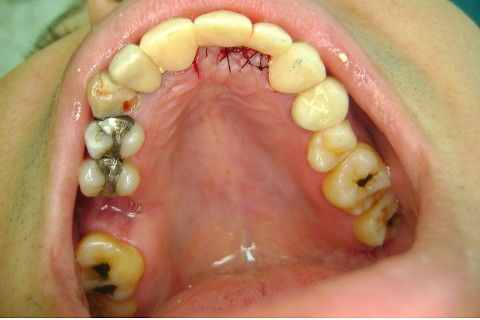

Cirurgia realizada hoje de manhã...No planejamento percebi medindo espessura do rebordo com especímetro que as medidas não estavam muito boas, ou o ideal, em torno de 4,5 a 5 mm ate´o terço médio do rebordo e melhorava no final, com 6 a 7 mm. Optei então por uma pequena expansão usando os expansores rosqueáveis. Aconteceu uma pequena fenestração na hora da fixação dos implantes, especialmente na região do 22 que fraturou o início da tábua óssea, mas não me preocupei porque não foi mais do que 2 mm de fratura em direção apical, o implante ficou infraósseo e com boa estabilidade (60 N no 21 e 40 N no 22). Esta fratura tb não deixou osso completamente solto, foi do tipo galho verde, deixei em posição e suturei normalmente. Só não fiz e nem estava planejado carga imediata mesmo, mais pelo motivo da oclusão inadequada do caso.

Fotos do caso